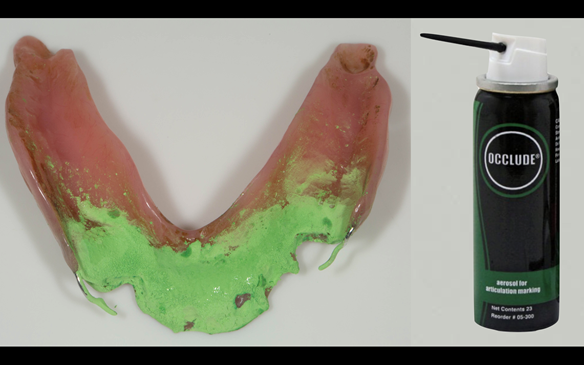

- Definitive dentures (Mk 2) – complete upper metal reinforced and lower cobalt chromium based partial of hygienic Scandinavian design to be made 9 - 12 months after extractions of all upper teeth and LR5 and LL4

The clinical situation and treatment process is shown in detail below with photographs.

The patient has been successfully rehabilitated and is now having periodontal maintenance from Syed Abad, Specialist in Periodontics at the practice. His quality of life has improved considerably. The clinical prosthodontics was provided by me and the technical work by Rowan.